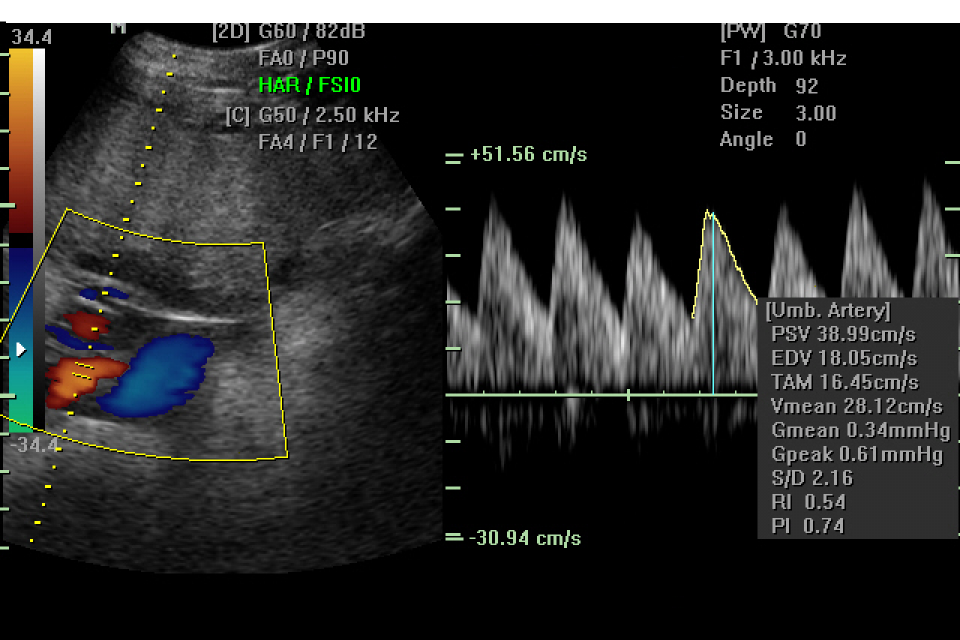

E` una ecografia che valuta principalmente la crescita del bambino, lo stato della placenta, la quantita` di liquido amniotico. Nel corso dell`esame vengono misurati la circonferenza cranica, la circonferenza addominale, il diametro della testa e la lunghezza del femore per poter stimare il peso fetale. Si controlla anche lo stato di benessere degli organi fetale per valutare che la loro formazione segua un decorso regolare rispetto al controllo effettuato durante l`ecografia morfologica. Vengono anche rilevati i movimenti del bambino sia respiratori che del corpo, che insieme alla valutazione del liquido amniotico costituiscono il profilo biofisico fetale, espressione dello stato di benessere del bambino.